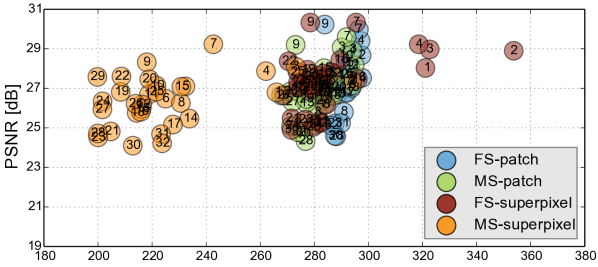

Reconstruction of Adult Brain MRI: Experiments on adult brain MR data using the Brainweb database [34] included introducing synthetic non-rigid motion artifacts as described in Sec. IV. Example slices of standard planes of original and corrupted data are depicted in Fig. 9. Comparative experimental results of SVR and PVR reconstruction methods are shown in Fig. 10 for PSNR, SSIM and CC. For all metrics, PVR shows an improved performance over SVR, particularly in presence of deformations with higher skewing angles. Further, we observe that superpixel-based PVR achieves similar performance as PVR using arbitrary square patches, while requiring a lower amount of input patches.

Comparative experiments of PVR variants were carried out on 32 fetal MR scans at gestational ages of approximately 20 weeks, presenting with challenging image corruption. Tab. I (a) & (b) show numerical results of evaluating individual stacks before reconstruction (baseline), and the final reconstructed image using square patches, superpixels and multi-scale variants of PVR. Statistical testing between baseline and PVR variants was carried out using paired T-Tests and differences between using fixed or multi-scale and using square patches or superpixels were assessed via Two-factor ANOVA with repeated measures. In Tab. I (a) & (b) the names of PVR variants are marked in bold if statistically significant differences have been found during analysis, i.e., FS and MS and/or Square Patches and Superpixel pairs are bold if the results between them differ significantly.

The evaluation of the reconstruction quality of a whole 3D image into a single-valued metric may not properly reflect the performance differences, as it is based on averaging values of all the pixels of all the input stacks. Furthermore, Tab. I indicates significant differences between variants of PVR but these differences have only minimal qualitative effect on reconstruction accuracy. Therefore, Fig. 12 evaluates the reconstruction quality of PVR additionally using dissimilarity heat maps based on the measured DSSIM (see Sec. IV-A). This approach allows further qualitative evaluation and allows for uncertainty visualization of PVR reconstructions.

Performance Analysis: We further evaluate the computational performance of each PVR variant. Measuring the overall runtime is not meaningful because this would be highly machine specific and would include data transfer overhead and non optimized functions. The runtime varied between 2000–4000s on our testing machines, depending on the system configuration. Instead we are analyzing the computational overhead introduced by PVR compared to SVR. The overhead can be measured by counting the number of processed patches and the number of additionally processed voxels. We compare these values to the achieved reconstruction quality in Fig. 13. Multi-scale superpixels show significantly better performance than other PVR variants and introduce the minimum necessary overhead while gaining the same image quality than more naïve PVR variants. Multi-scale superpixels are potentially five times faster than other variants.

PVR introduces a considerable computational overhead to the reconstruction stage of fetal MR image processing pipelines. We have evaluated the amount of necessary additional redundant information to give a general idea about the expected runtime of different PVR variants. Patches based on multi-scale superpixels are significantly more efficient than a naïve implementation of overlapping square patches, while maintaining a similar reconstruction accuracy. Quantitatively, square patches perform slightly better for the brain, which is most likely due to the rigid nature of the enclosing skull. Superpixel-based patches achieve better results for regions that are likely affected by non-rigid movements like the placenta and the whole uterus.